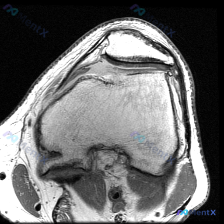

本次提供的是膝关节MRI矢状位T2加权图像,具体影像学发现如下:

- 骨骼结构:股骨远端髁前部及滑车无明显骨折,胫骨平台关节面完整无塌陷,髌骨结构未见明显异常;股骨远端周围皮下软组织可见明显异常高信号,提示软组织水肿。

- 关节软骨:髌股关节间隙内,髌骨关节面软骨信号欠均匀,存在明确的软骨信号异常。

- 核心阳性发现:髌上囊区域可见大范围极高信号液体聚集,提示大量关节积液,积液信号均匀,考虑为单纯性渗出;髌前软组织也存在大范围片状高信号,提示明显软组织水肿/炎症。

- 其他结构:股四头肌腱轮廓可见,但周围水肿信号明显,无法排除肌腱损伤;交叉韧带因层面限制无法全面评估;髌下Hoffa脂肪垫信号欠均匀,伴周围水肿,考虑为继发性炎症改变。